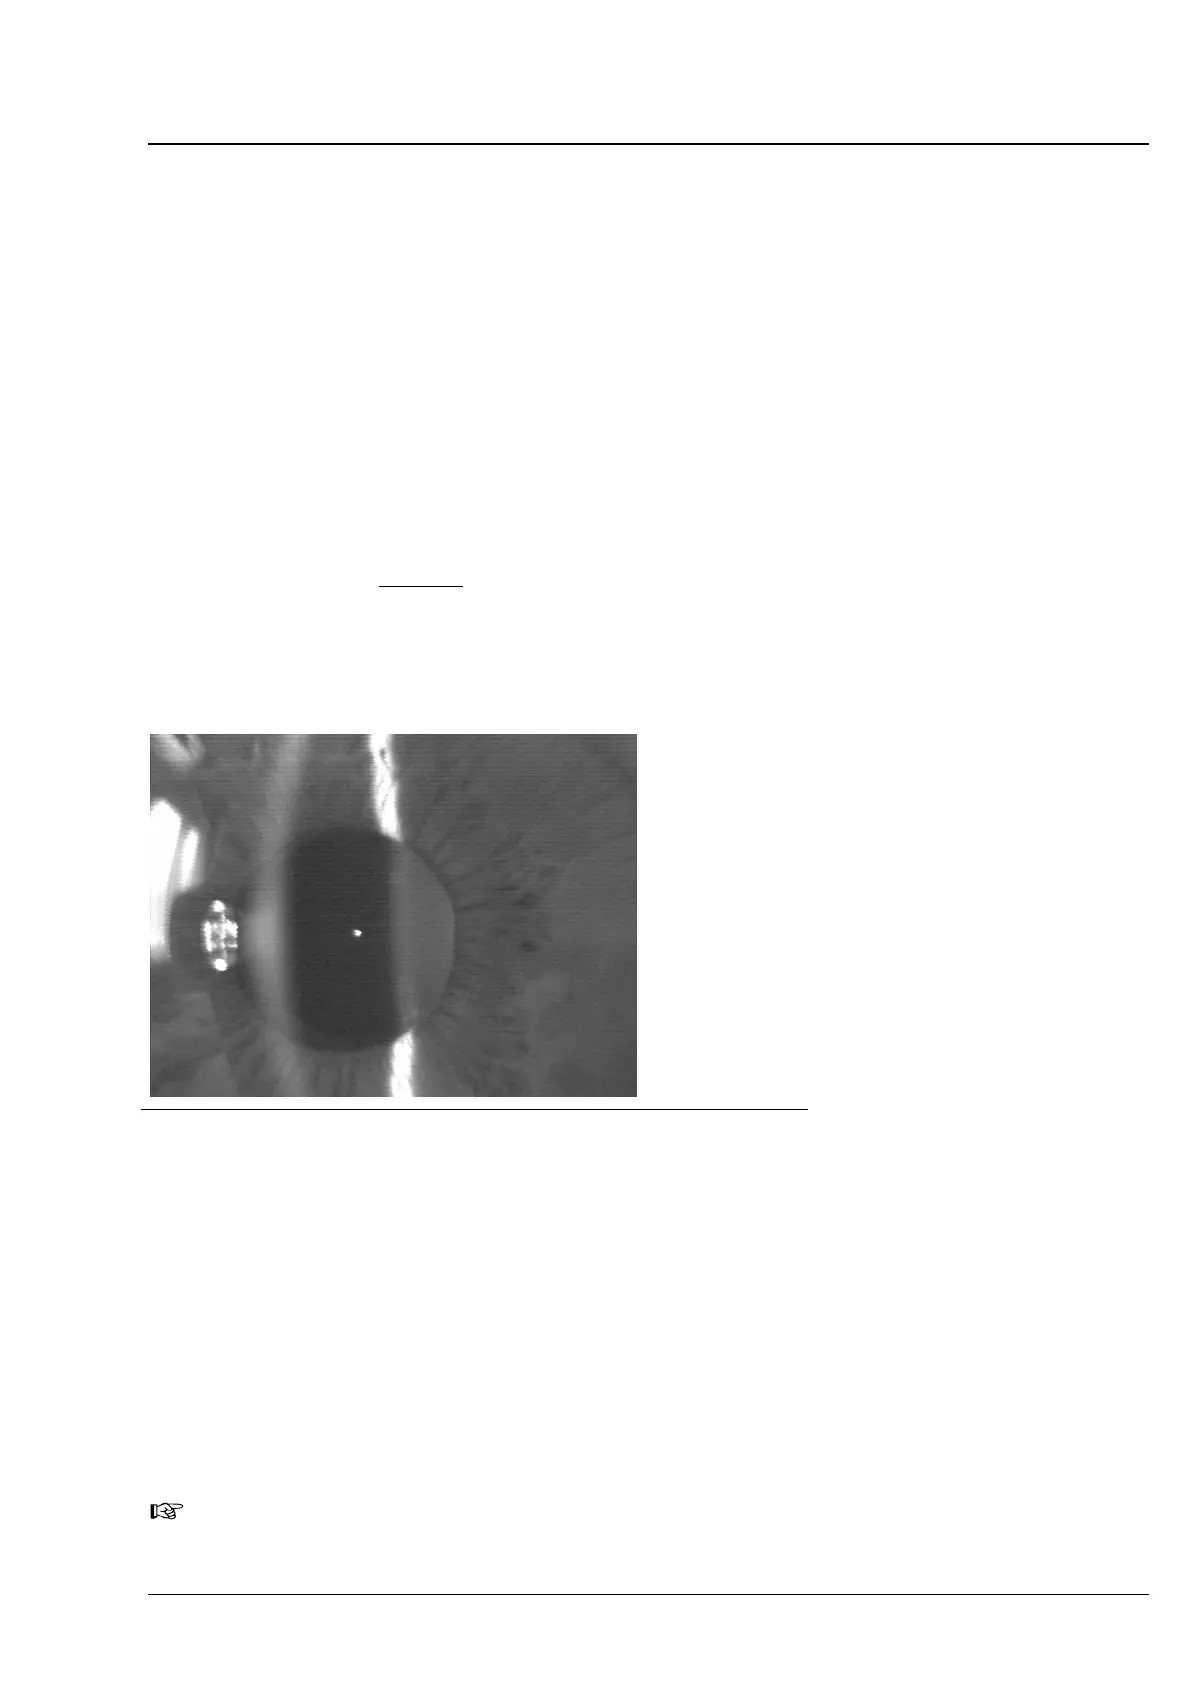

Fig. 62 Coupe lumineuse réglée de manière idéale pour la mesure de la profondeur

Sur l'écran apparaît une image (coupe lumineuse par le segment avant

de l'Ĺil) qui est semblable à celle près de la lampe excitatrice. Par un

déplacement latéral sur le joystick, l'appareil doit être ajusté de telle

sorte par rapport à l'Ĺil du patient que:

q l'image du point de fixation apparaisse aussi précise que possible sur

l'écran,

q que l'image de la cornée (dans le cas de l'Ĺil droit vers la gauche,

dans le cas de l'Ĺil gauche vers la droite) soit exempte de reflets (pour

des raisons liées au système, cette photo est floue ) et

q que l'image de l'arête avant de la lentille soit visible dans la pupille.

L'image du point de fixation devrait se situer à proximité (pas

dans!) l'image de la coupe de la lentille.